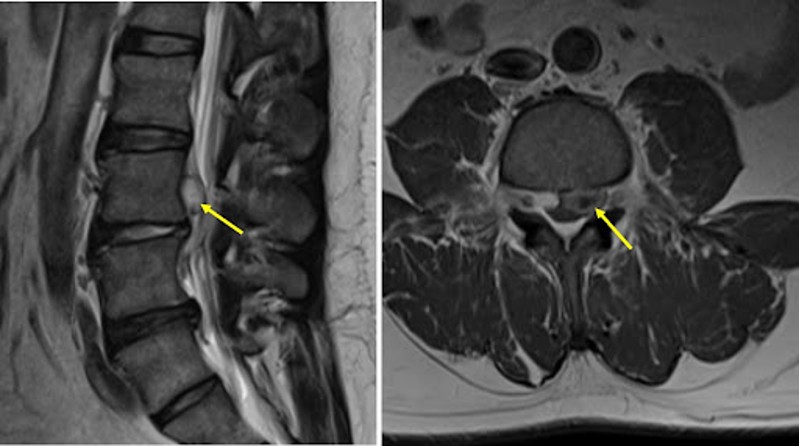

Disc extrusion is a type of intervertebral disc herniation in which the nucleus pulposus (the inner gel-like material) breaks through the annulus fibrosus (the tough outer ring) but remains connected to the main disc. It represents a more advanced stage than a disc protrusion, with the herniated material extending beyond the confines of the annulus.